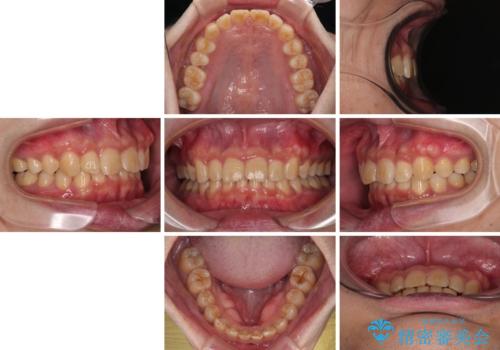

上顎歯列を遠心移動させたことで、前歯の叢生が解消されても前歯が前突することなく、左右ともに理想的な咬み合わせを達成することができました。